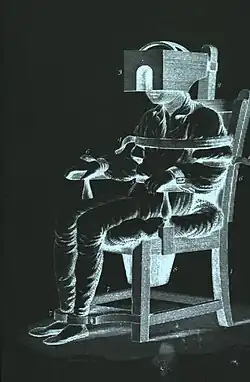

Electroconvulsive Therapy

Electroconvulsive Therapy or ECT for short is a medical treatment that involves sending electrical currents through the brain.[30] ECT was created by Italian neurologists Ugo Cerletti and Lucio Bini in 1938. Their invention quickly spread to North America and was a common practice in the United States in the late 20th century. ECT was often used to treat a wide range of mental disabilities.[31] Autism, ADHD, OCD, and other mental disorders were often misunderstood during the 20th century, therefore, most doctors treated them all the same way through ECT.[32] ECT was used as a broad treatment plan for those experiencing any mania. Specific treatments, therapy, and medications for each separate illness and disability wouldn't become used in the public until the 21st century.